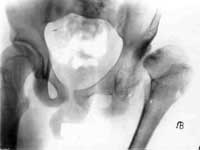

5.Результат лечения.